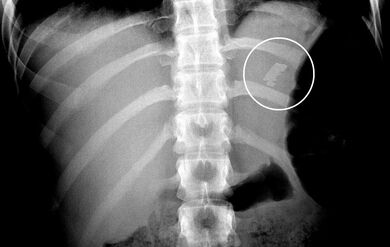

Die 23-jährige Patientin wird vom Notarzt nach selbst beigefügten Schnittverletzungen am Hals und verschluckter Rasierklinge eingeliefert. Bezüglich des Abdomens wurden keine Beschwerden angegeben. Das Röntgenbild zeigt eine halbe Rasierklinge in Projektion auf den Magen ohne freie Luft. Bei nüchterner Patientin erfolgt die ÖGD unter Sedierung. Hier zeigt sich die Radierklinge im Corpus. Was nun